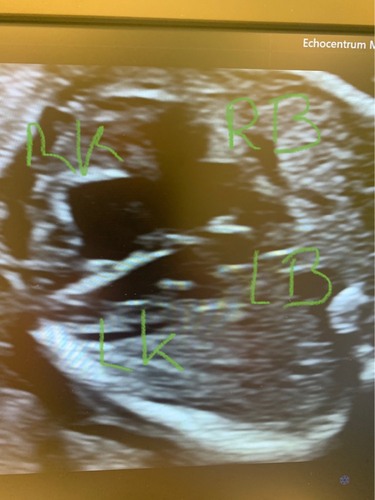

Ik weet niet of je het duidelijk kunt zien.. Het lijkt erop dat de linker boezem kleiner is dan de rechter.. Op internet vind ik van alles maar ook weer helemaal niks..